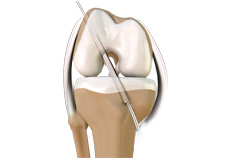

ACL Reconstruction

The anterior cruciate ligament is one of the major stabilizing ligaments in the knee. It is a strong rope like structure located in the centre of the knee running from the femur to the tibia.